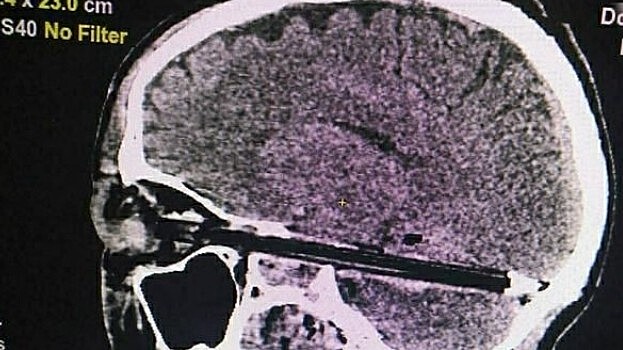

Ростовские хирурги извлекли шариковую ручку из глаза пациента

Ростовчанин был доставлен в больницу в тяжелом состоянии После диагностики стало понятно, что ручка повредила глазное яблоко и затронула часть головного мозга. Медикам пришлось делать срочную трехчасовую операцию. Пациента перевели в реанимационное отделение. «Ручка прошла в миллиметре от важнейших сосудов и ствола головного мозга, чудом не повредив их», — рассказали в краевом Минздраве. Правоохранителям предстоит выяснить, каким образом канцелярский предмет попал в глаз 38-летнему мужчине.